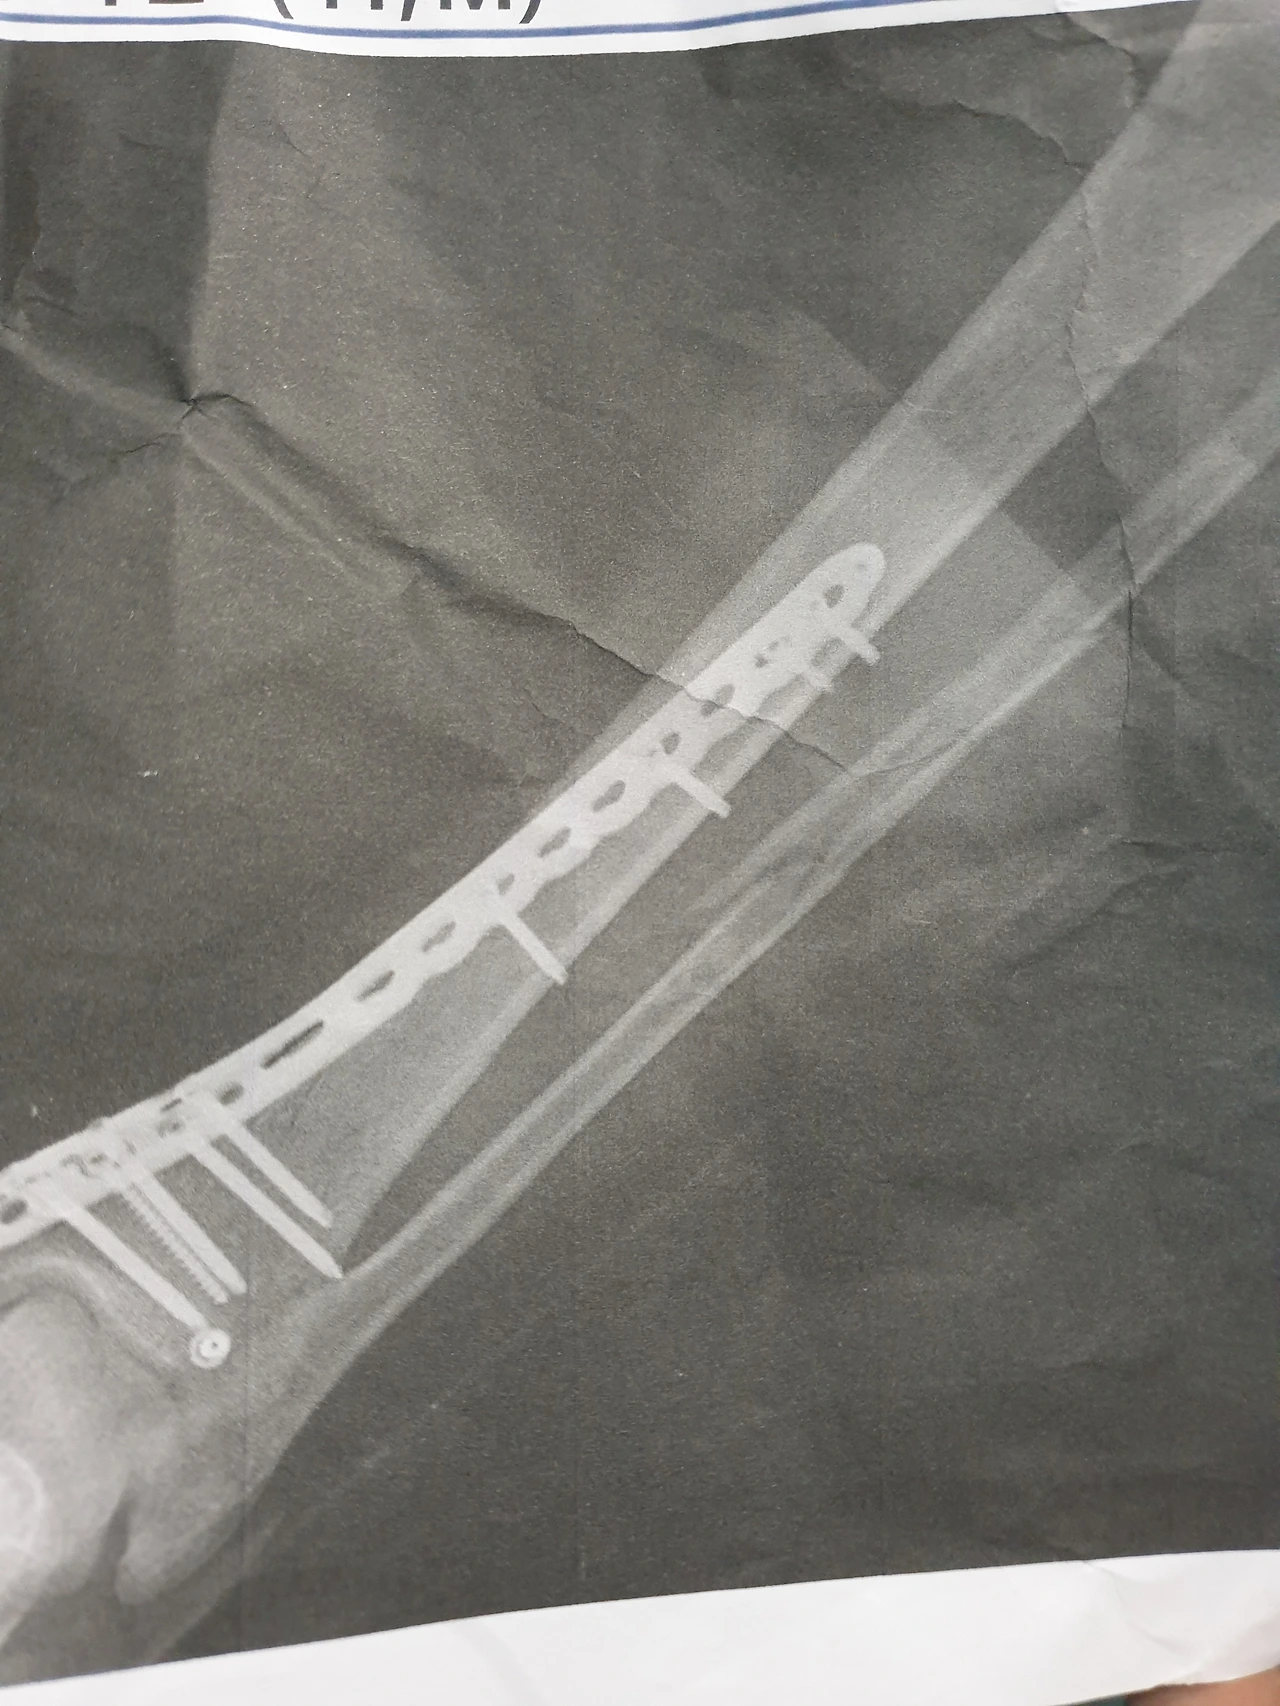

철판과 함께 피스 7개를 밖은 수술이 끝난 후 담당의는 수술이 잘됐으니 걱정 말라는 이야기를 남겼다.

그리고 2주 정도의 입원을 마치고 통원치료로 변경하기 위해 통깁스를 할 때 즈음 의사는 네 수술부위의 엑스레이 사진을 주며 기념으로 받으라는 이야기를 해주었다.

우선 신기한 경험이기는 하기에 주는 데로 받기는 했지만 무엇을 기념하라는 건지는 도저히 이해가 가질 않았다.

게다가 정강이 뼈 두 개 중 철판을 박지 못 한 뼈가 산산이 부서진 사진을 가리키며 폭파라도 된 듯 신기하게 터진 뼈가 보이죠. 이것도 붙을 거니 걱정 마세요.

라는 말을 남겨주었다. 폭파라도 된 듯 펑하고 터져버린 내 뼈가 과연 어떤 로직과 프로세스를 통해서 다시 붙을 진 의문이었지만 의사에게 이런저런 걸 물어볼 멘털도 아니었더 나는 주섬 주섬 짐을 챙기고 병원을 나섰다.

이틀 전 수술을 받은 병원에 가서 담당의의 진료를 받았다. 1달 만에 다시 보는 순간이었고 수술 후 10주가 지난 시점이었다. 은근 기대를 하고 다시 찍은 엑스레이 사진의 내 뼈들은 고대로였다.

나이도 있겠거니와 사실 산산이 부서진 뼈들이 그리 쉽게 붙을 거라고는 예상을 하지 않았지만 그걸 예상한 것과 다시 확인하는 순간의 심리적 갭은 꽤나 컸다.

. '철판 튼튼하게 박혀있으니 절대 다시 안 부러집니다. 걱정 마세요.'